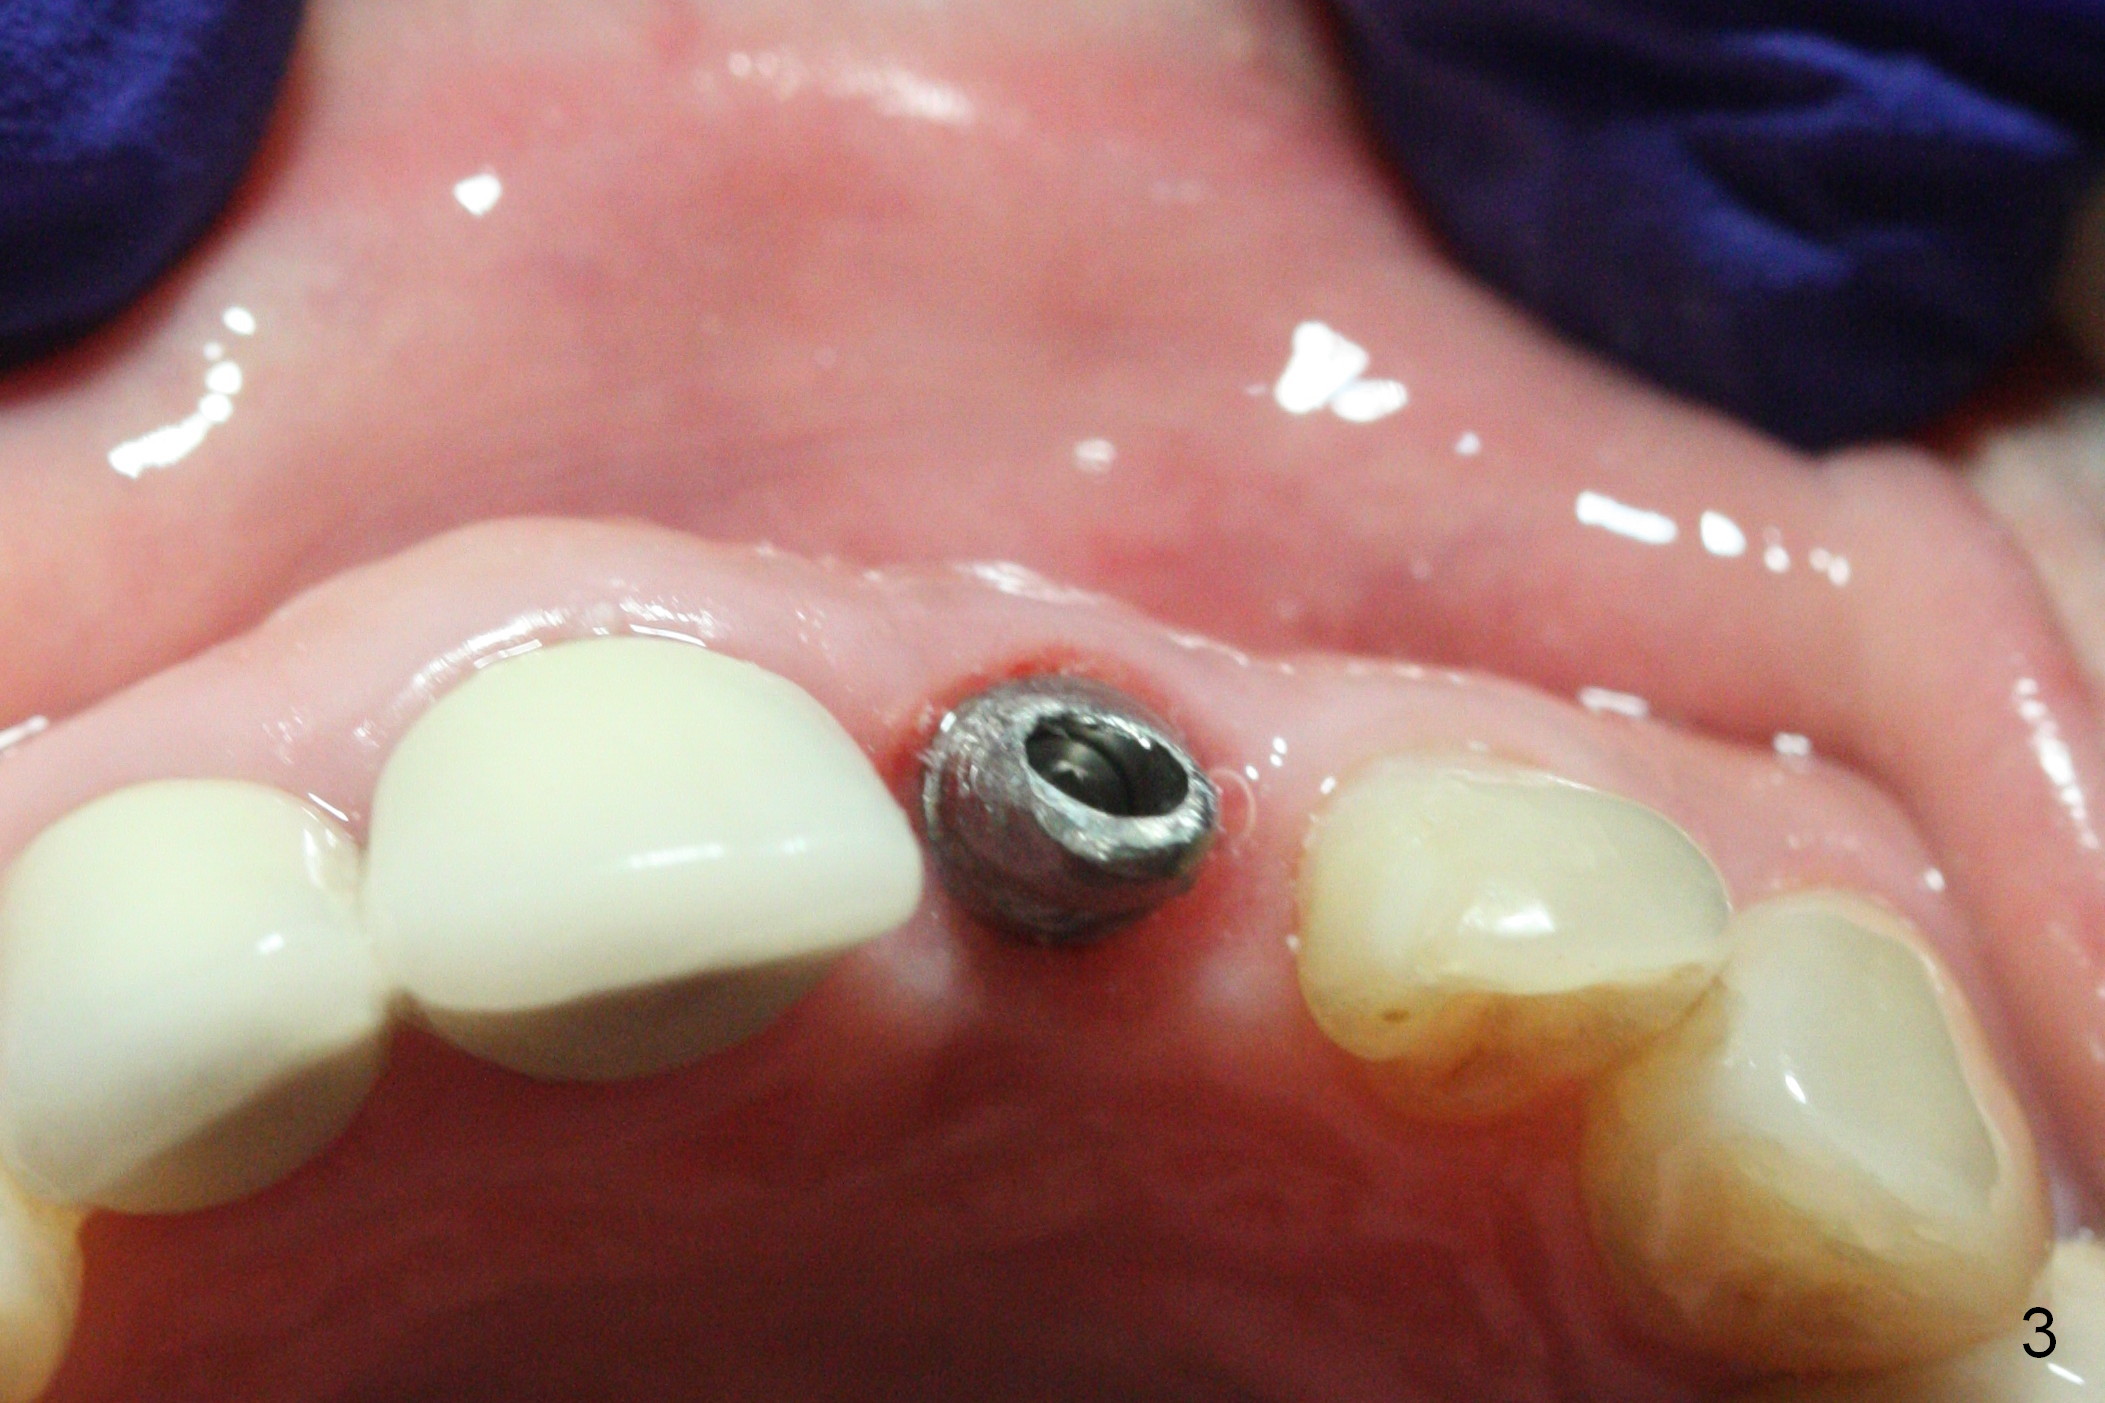

When a permanent crown (Fig.1 C) is seated 5 months postop, it looks too long and bulky (as well as metal show through cervically), which is in turn due to buccal placement of the crown (Fig.2) and abutment (Fig.3). By mistake, abutment is changed from 4.5x15°, 3 mm cuff to 4.5x15°, 2 mm cuff (Fig.4-6); the profile appears to improve. After prep (buccoincisal (Fig.4 ^) and linguoincisal), impression is taken. The gold coating in the buccocervical area is untouched so that there should be no or minimal metal show through. Please make a new crown as cosmetic as possible (not too bulky, especially buccocervical). If you feel that the result will be the same as before, return the case. The angled abutment may be changed 25°. In fact the new crown looks better.